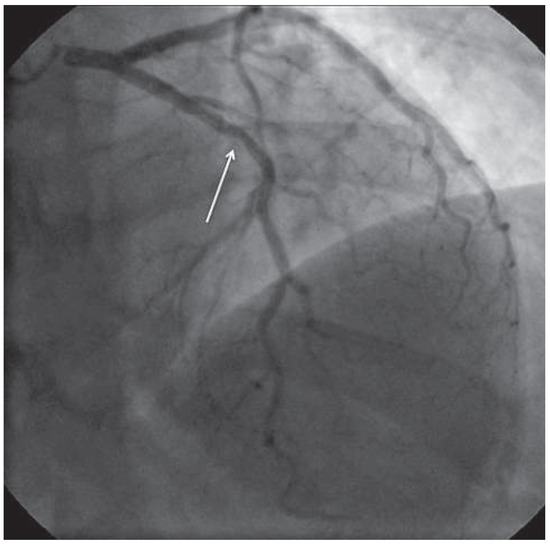

2 pages, 1507 KB

Case Report

Coronary Spasm Provocation Testing: Still Useful?

by Felipe Andres Molina Jaque, Andrew Christopher Rahardja, Timothy Watson and Mark Webster

Cardiovasc. Med. 2014, 17(2), 46; https://doi.org/10.4414/cvm.2014.00213 - 19 Feb 2014

Cited by 1 | Viewed by 153

Abstract

This short and interesting case demonstrates very aptly the potential clinical utility of provocation testing for coronary artery spasm and briefly discusses the uncertainty encountered in interpreting the test. Full article

Show Figures

Figure 1